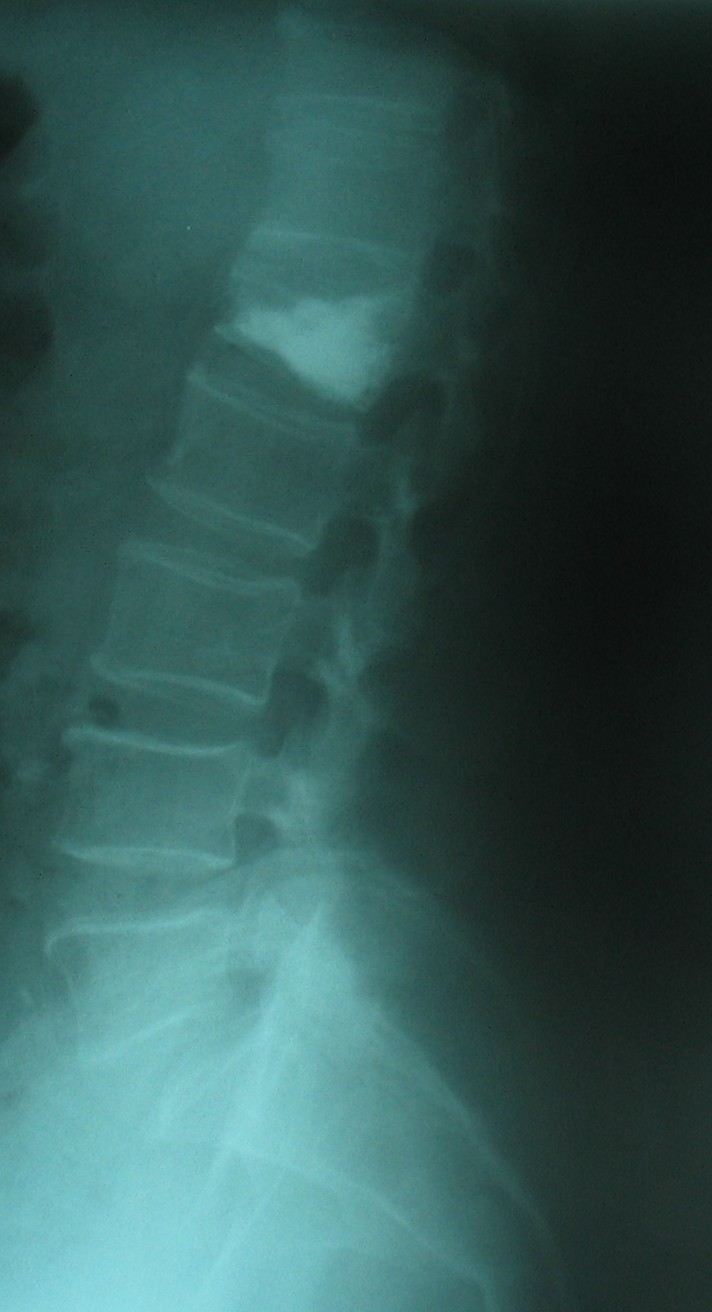

Kemik Erimesine (Osteoporoz) Bağlı Omurga Kırığı: İleri yaşta osteoporoz, yaşlılık ve/veya menopoza bağlı kemik kitlesinin azalması nedeniyle oluşur. Kemikleri zayıflatan bu sorun nedeniyle basit travmalarda bile kemikler kırılabilir hale gelir. En çok kırılan kemikler omurga ve kalça kemikleridir. Osteoporozun çok ileri olduğu bazı durumlarda hasta aksırınca bile omurgası kırılabilir. Bu durumda hastaya kemik çimentosuyla dolgu tekniği (vertebroplasti) uygulanabilir. Ancak tekrarlayabileceği göz önünde bulundurularak kemik erimesine yönelik ilaç tedavisi unutulmamalıdır. Hastalarda en sık ortaya çıkan şikayet sırt ya da bel ağrısıdır. Bazen çökme kırıkları sonucu olan ağrı hastayı çok rahatsız etmez ama oluşan deformite sonucu hasta doktora başvurur. Yaşlılarda Kifoz: Yaşlanan omurgada hem osteoporotik kırıklar hem de disklerde oluşan dejenerasyonla beraber kifoz oluşabilir. Bu durum bir yandan hastada solunum sorunları oluştururken diğer yandan günlük aktiviteleri kısıtlar. Yaşlılarda Skolyoz: İleri yaşta skolyoz ya dejeneratif omurga sorunları sonucunda ya da geçmişte var olan skolyozun artmasıyla oluşabilir. Birinci durum sinirlere bası nedeniyle sıklıkla bacaklara yayılan ağrı ile beraberdir.

Kemik erimesine (osteoporoza) bağlı omurga kırığı olan hastada vertebroplasti (çimento ile dolgu) tedavisi